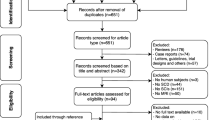

Patients and methods

This is a cross-sectional case–control study conducted at the Pediatric Hematology Oncology department, Children’s Hospital, Ain Shams University. Participation was voluntary after informed consent and assent were obtained from legal guardians of all participants and their children. The procedures applied in this study were approved by the institutional regulatory board of the Pediatric and Radiology department as well as by the Ethical Committee of Human Experimentation of Ain Shams University and were in accordance with the Helsinki Declaration of 1975, as revised in 2008.

Study population

Thirty-two adolescents and young adults with SCD, 13 females (40.6%) and 19 males (59.4%), with their mean age of 15.25 ± 3.69 years, were recruited at their steady state defined as a point in time where the patient in question is not experiencing an acute painful crisis or any changes due to therapy) [8]. In addition, fifteen patients with BTM, 8 (53.3%) females and 7 (46.7%) males, with their mean age of 19.40 ± 4.31 years, were recruited as a comparative iron overload syndrome. Furthermore, eleven healthy controls—subjects who had not history of any neurological disease, blood transfusion, or any condition that would affect the body iron content, 6 females (54.5%) and 5 males (45.5%)—their mean age was 17.73 ± 4.84 years.

Recruited subjects should be able to perform MRI and neuropsychiatric assessment. Subjects known to have contraindications for MRI, those with myocardial infarction, cardiac failure, or and liver cell failure; those with history of neurological disease, head trauma, or neurosurgery; and those treated with any medications affecting the cognition, memory, and behavioral were excluded. None of SCD patients had diabetes or micro-albuminuria, and all of them had previously experienced vaso-occlusive crisis; clinical characteristics among the studied thirty-two SCD patients are illustrated in Table 1.